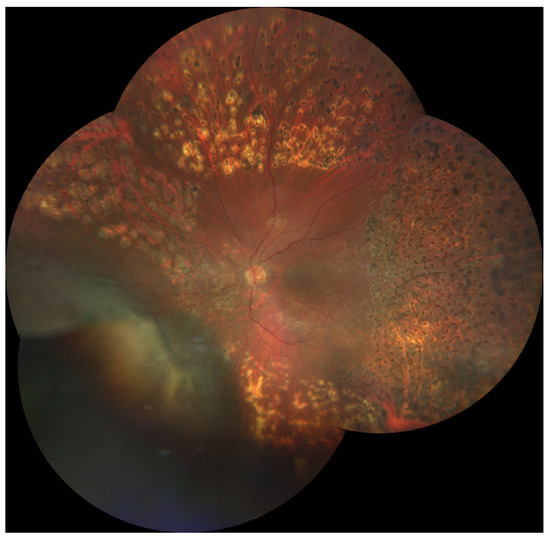

3.1. Radiation (Chorio)Retinopathy